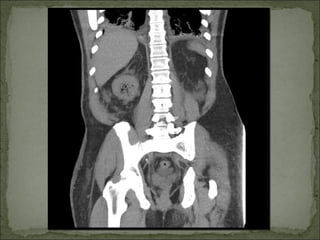

Se solicita TAC abdomino-pélvico.

Sepsis grave de origen urológico: Pielonefritis

enfisematosa.

Valorado por urología. Sesolicita TAC abdomino-pélvico.

Sepsis grave deorigen urológico: Pielonefritis enfisematosa. Descompensación diabética no cetósica secundaria a Pielonefritis Enfisematosa. Insuficiencia renal aguda secundaria. Celulitis abdominal e inguinoescrotal derecha.